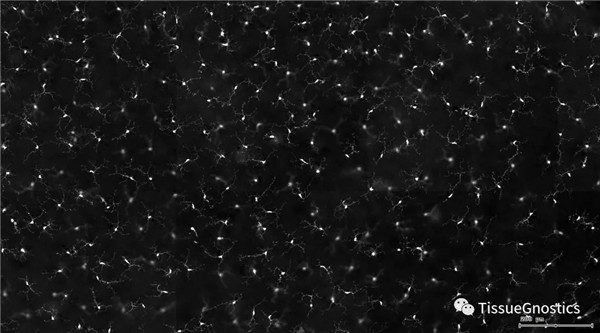

視網(wǎng)膜熒光樣本中小膠質(zhì)細(xì)胞胞體、神經(jīng)纖維識別、血管識別、血管斑點(diǎn)識別、神經(jīng)元與血管的距離分析。

單通道灰階圖(↑:FITC,↓:Texa Red)

根據(jù)染色強(qiáng)度,染色面積,細(xì)胞形態(tài)學(xué),利用正反向回溯功能和設(shè)門圈選Gating,排除雜質(zhì),細(xì)胞碎片,黏連細(xì)胞(綠色框線標(biāo)記),獲得神經(jīng)元胞體,(粉色框線標(biāo)記),并將胞體按照面積分為兩類(散點(diǎn)圖)。

由于該視網(wǎng)膜樣本是標(biāo)記的小膠質(zhì)細(xì)胞,根據(jù)面積將神經(jīng)胞體分為兩類(Small bodycell,Big bodycell),反向回溯Big bodycell中的細(xì)胞后,應(yīng)用Input Gate功能篩選短粗的神經(jīng)纖維,作為激活態(tài)的小膠質(zhì)細(xì)胞。